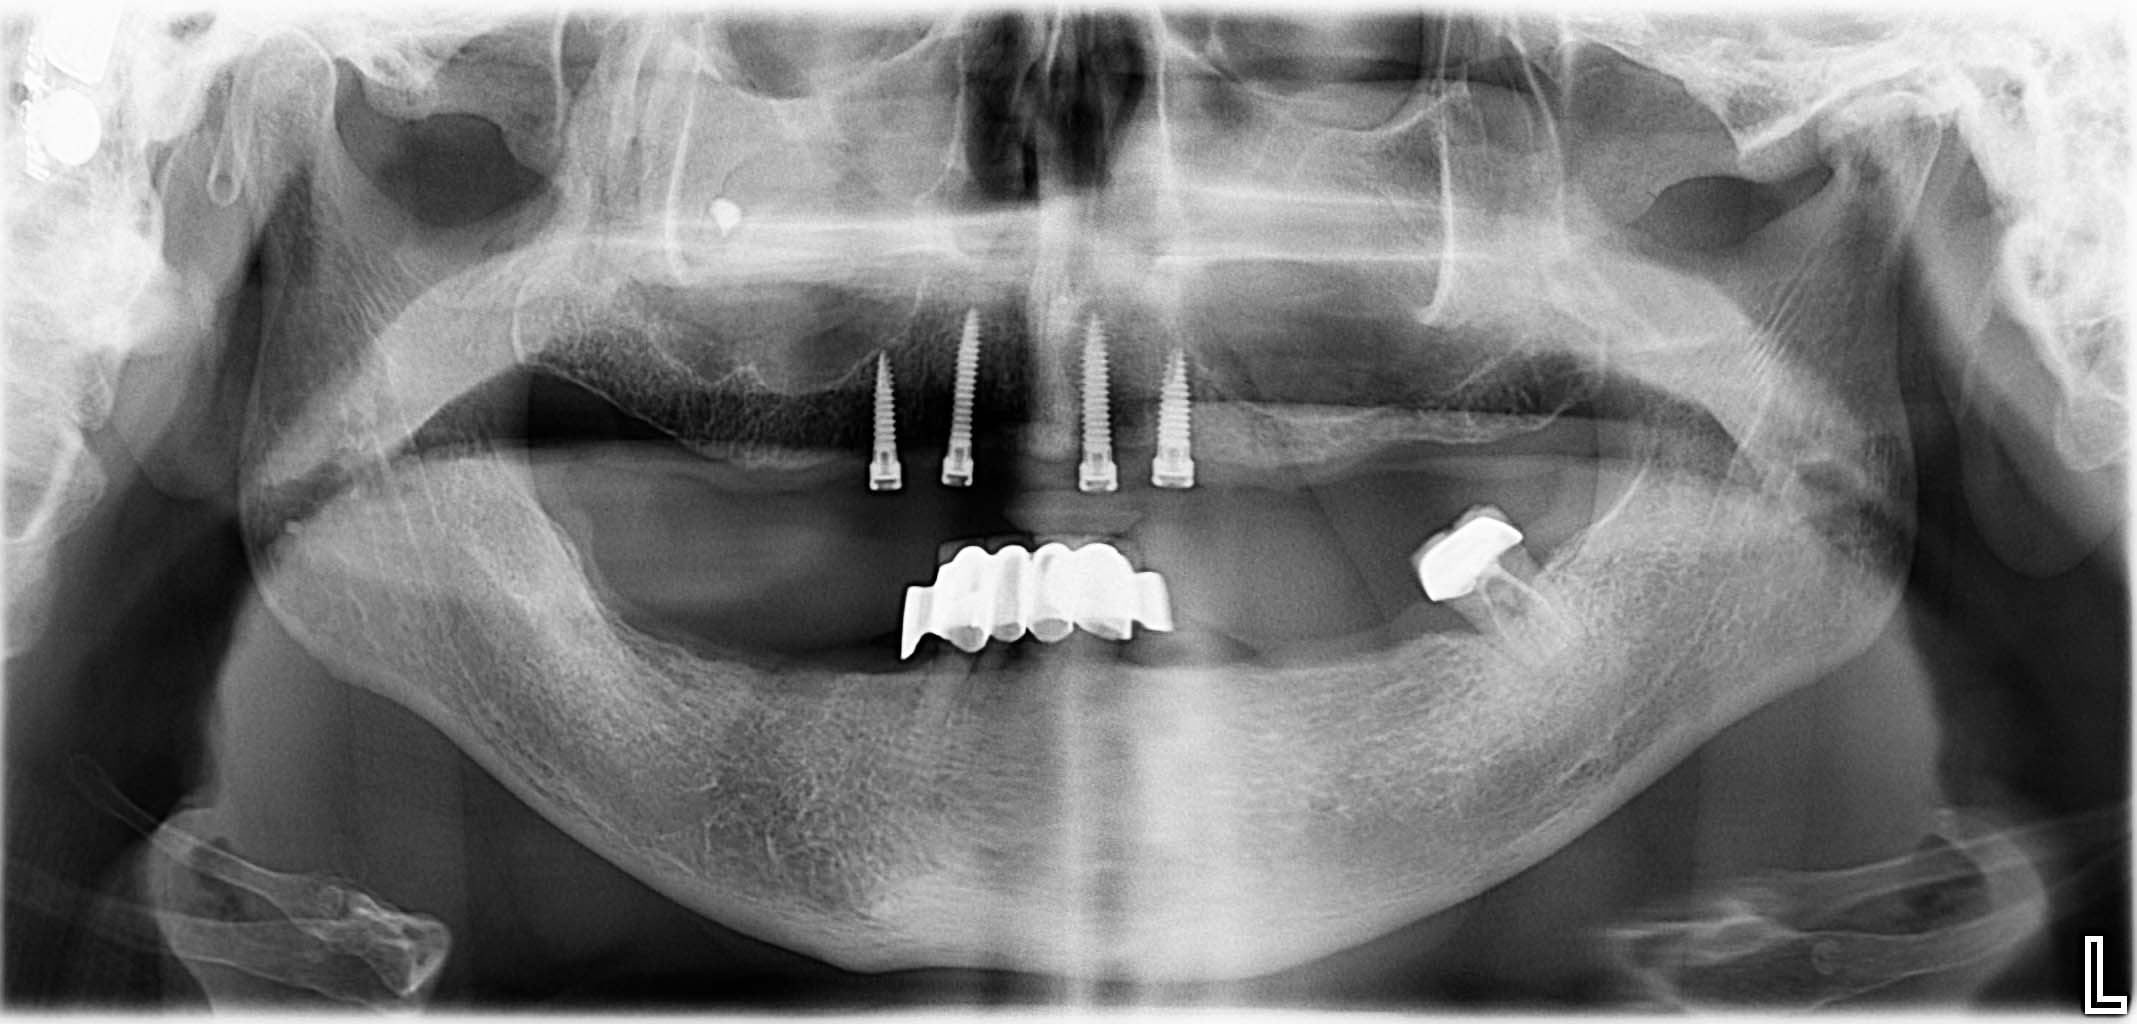

Ausgangssituation: Zahn 36 mit apikaler Beherdung, nicht erhaltungswürdig